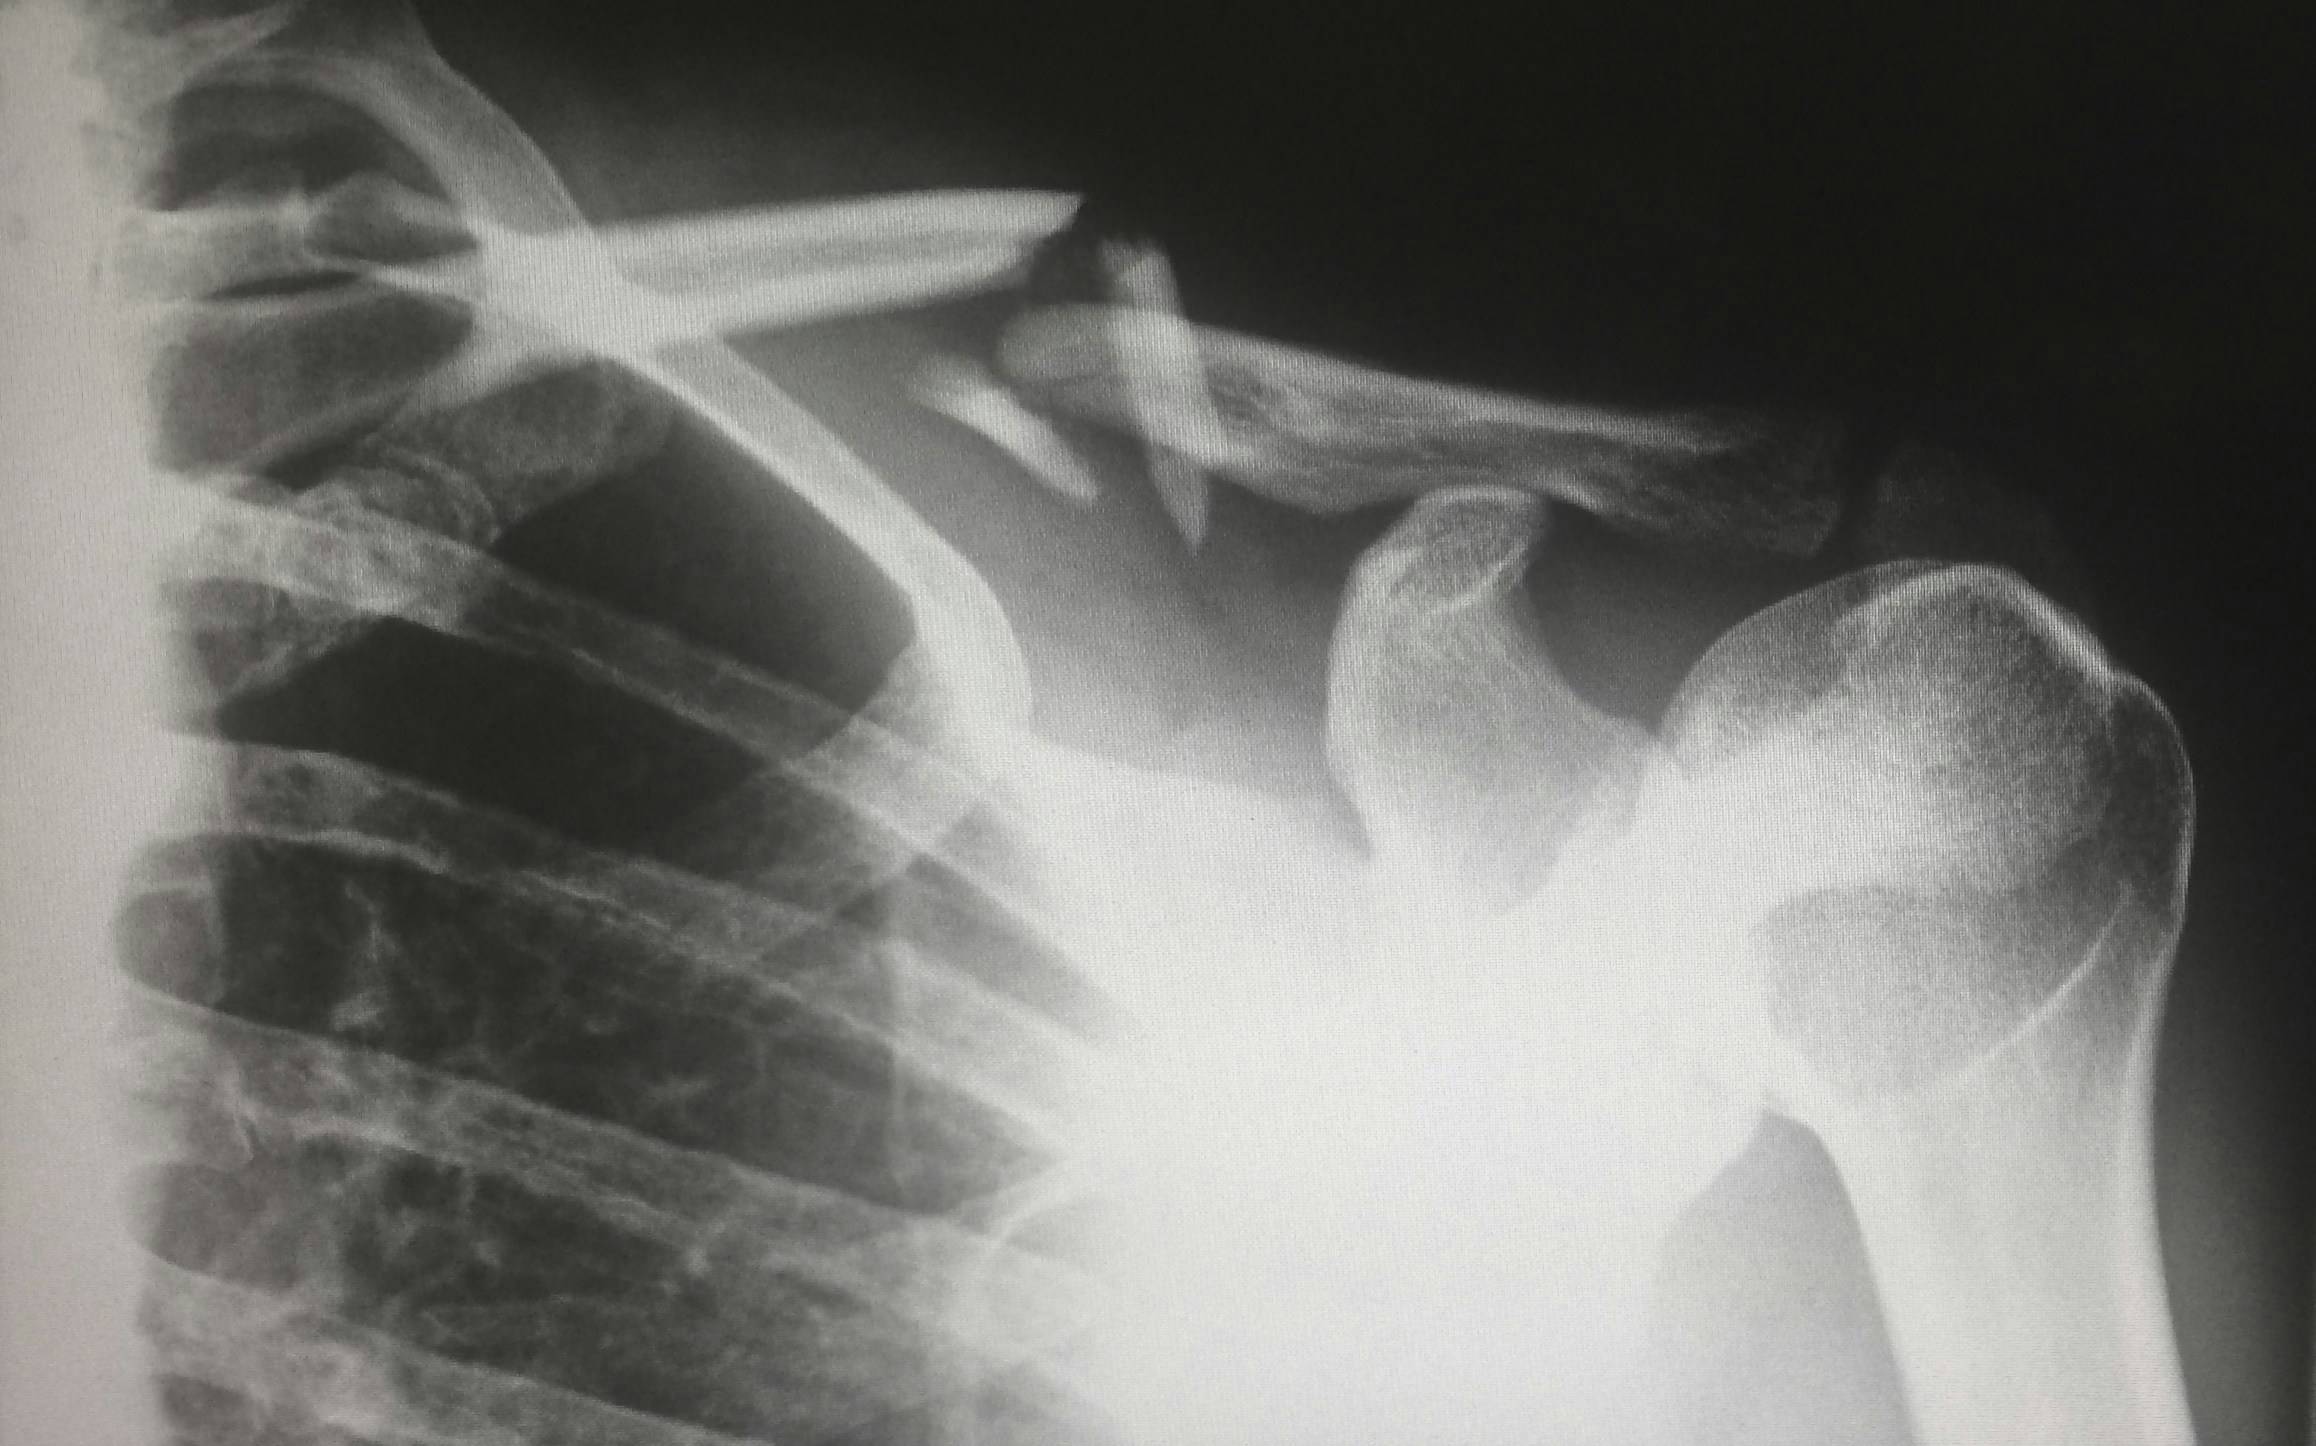

Neben den starken Schmerzen und der Bewegungseinschränkung kann es auch zu einer leichten Ausbeulung oder Vertiefung kommen, je nach Bruchstelle und -art. Sehr selten gibt es offene Brüche. Meist bricht das Schlüsselbein in der Mitte, wo es am dünnsten ist. Außerdem entstehen Schwellungen und es können Reibe- und Knirschgeräusche zu hören sein.

Bestätigt das Röntgenbild die Fraktur, stellt sich die Frage: Konservativ behandeln oder doch operieren? Bis vor kurzer Zeit wurden die meisten Brüche mit einem sogenannten Rucksackverband behandelt. Bei diesem Verband wird die Schulter durch ein spezielles Verbandsystem so nach hinten gezogen, dass das Schlüsselbein in Position bleibt und gerade zusammenwachsen kann. Bei einfachen, glatten Brüchen dauert es dann bis zu sechs Wochen, bis der Arm schon wieder leicht bewegt werden kann. Leichtes Training, das die Schulter nicht belastet, ist erst nach zehn bis zwölf Wochen wieder möglich. Heute wird der Verband auch weggelassen, wenn der Bruch sehr einfach ist – oft ist die Heilung dann ohne Verband genauso schnell wie mit Verband.

Kompliziertere Frakturen werden heute eher operiert – dazu wird das Schlüsselbein durch Platte und Schrauben zusammengehalten, die später auch wieder operativ entfernt werden müssen. In der Regel ist die Heilung nach einer OP etwas schneller – immer abhängig von der Komplexität des Bruches und anderen Verletzungen rund um die Fraktur. Dort verlaufen viele Nerven und Gefäße, die durch den Sturz ebenfalls beschädigt werden können.